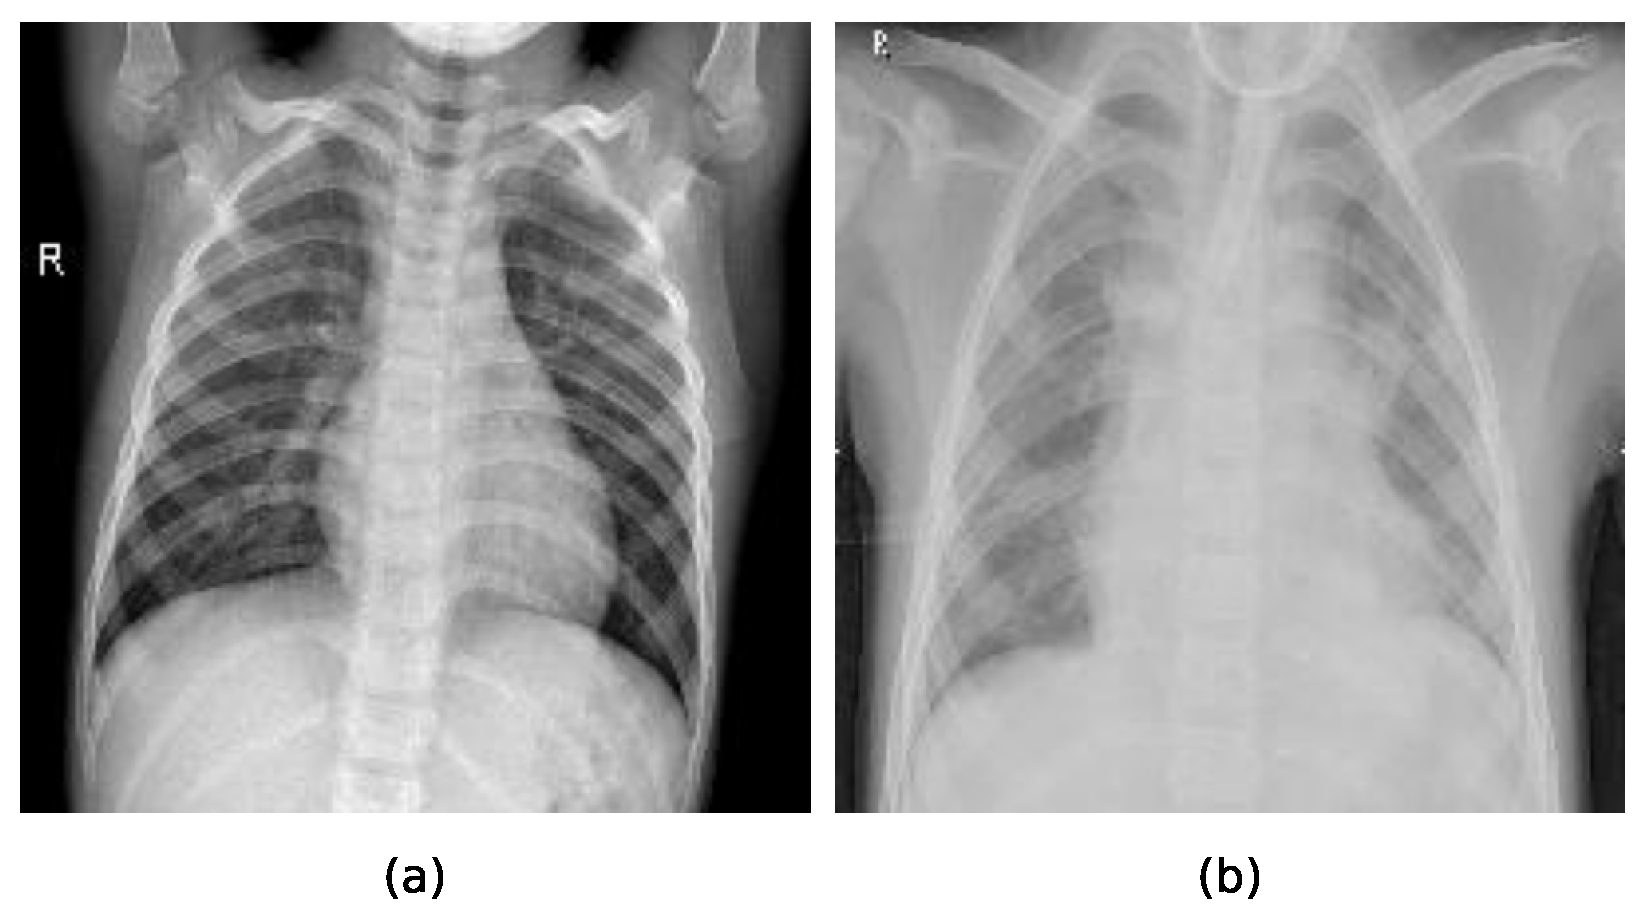

Two sample chest X-ray images used for training and evaluation of the compared methods can be observed in Figure 5, where the sample a represents the X-ray image of a healthy lung, while the sample b represents the X-ray image of lungs indicating pneumonia.

Figure 5. Samples representing each of the categories of X-ray images in the dataset: (a) represents an X-ray image of healthy lungs, (b) represents X-ray image of lungs indicating pneumonia.